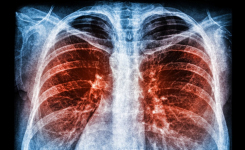

This multicenter prospective study evaluated nanopore-based targeted next-generation sequencing to detecting M. tuberculosis and drug resistance directly from non-sputum specimens.